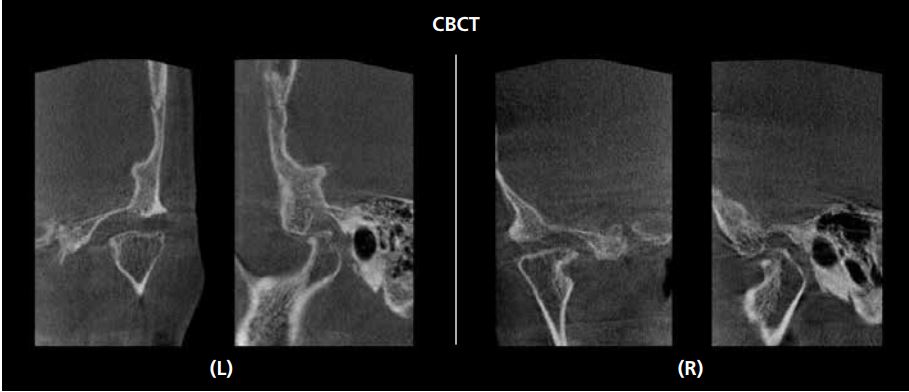

Đánh giá vị trí hàm dưới bằng X-quang khớp thái dương hàm (TMJ) hoặc CBCT

Để đánh giá vị trí của lồi cầu trong hố khớp thái dương hàm, độ ổn định của vị trí hàm dưới cũng như phát hiện các vùng thấu quang gợi ý tình trạng viêm, sự dẹt của lồi cầu hoặc hình thành gai xương (osteophyte) thì chụp X-quang khớp thái dương hàm hoặc CT chùm tia hình nón là những phương tiện hữu ích.

Dựa trên kết quả của lần thăm khám ban đầu này, chúng ta có thể dự đoán liệu có thể đạt được hiệu quả hít dính tốt ở hàm dưới hay không, hoặc liệu có cần thiết kế một loại hàm giả điều trị đặc biệt hay không.